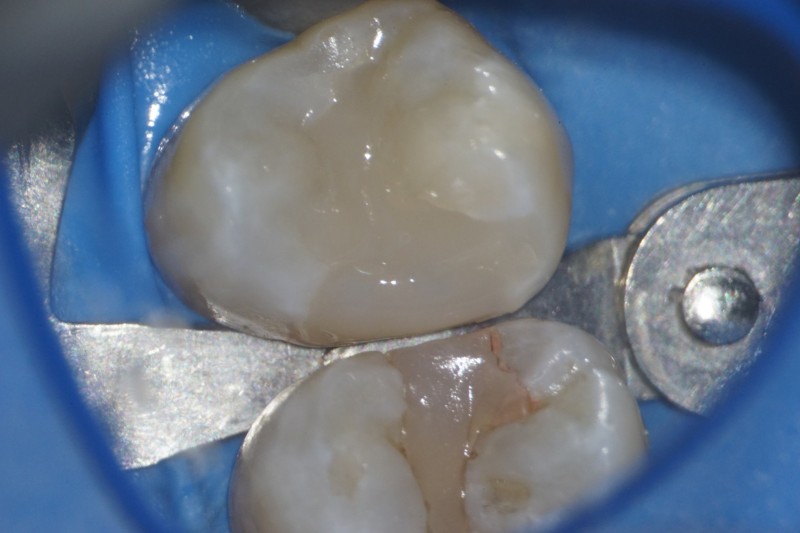

ダイレクトボンディングで修復しました。

セパレータを外して完成です。

※隣の歯の詰め物も、後日ダイレクトボンディングで修復しました。